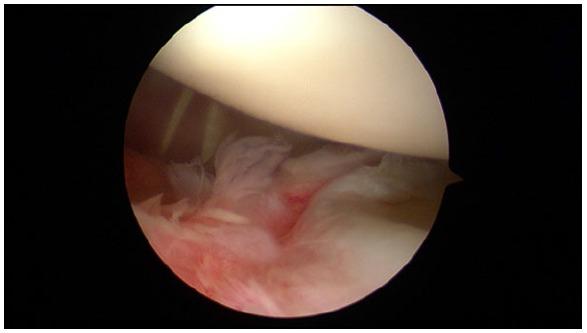

The glenohumeral joint is a ball-and-socket joint that is inherently unstable and thus, susceptible to dislocation. The traditional and most common anatomic finding is the Bankart lesion (anterior-inferior capsule labral complex avulsion), but there is a wide variety of anatomic alterations that can cause shoulder instability or may be present as a concomitant injury or in combination, including bone loss (glenoid or humeral head), complex capsule-labral tears, rotator cuff tears, Kim´s lesions (injuries to the posterior-inferior labrum) and rotator interval pathology.

Due to the complex anatomy of the shoulder and the large range of movement of this joint, a wide variety of anatomic injuries and conditions can lead to shoulder instability, specially present in young population. Recognizing and treating all of them including Bankart repair, capsule-labral plicatures, SLAP repair, circumferential approach to pan-labral lesions, rotator interval closure, rotator cuff injuries and HAGL lesion repair is crucial to achieve the goal of a stable, full range of movement and not painful joint.

盂肱关节是球窝关节,本质上不稳定,因此易发生脱位。传统且最常见的解剖学发现是Bankart损伤(前下关节囊盂唇复合体撕脱),但存在多种可导致肩部不稳定或可能作为伴随损伤出现或合并存在的解剖学改变,包括骨质流失(肩胛盂或肱骨头)、复杂的关节囊盂唇撕裂、肩袖撕裂、Kim损伤(后下盂唇损伤)和旋转间隙病变。

由于肩部解剖结构复杂且该关节活动范围大,多种解剖学损伤和病症可导致肩部不稳定,尤其在年轻人群中常见。识别并治疗所有这些损伤,包括Bankart修复、关节囊盂唇折叠术、SLAP修复、全盂唇病变的圆周入路、旋转间隙闭合、肩袖损伤和HAGL损伤修复,对于实现稳定、全范围活动且无痛关节的目标至关重要。